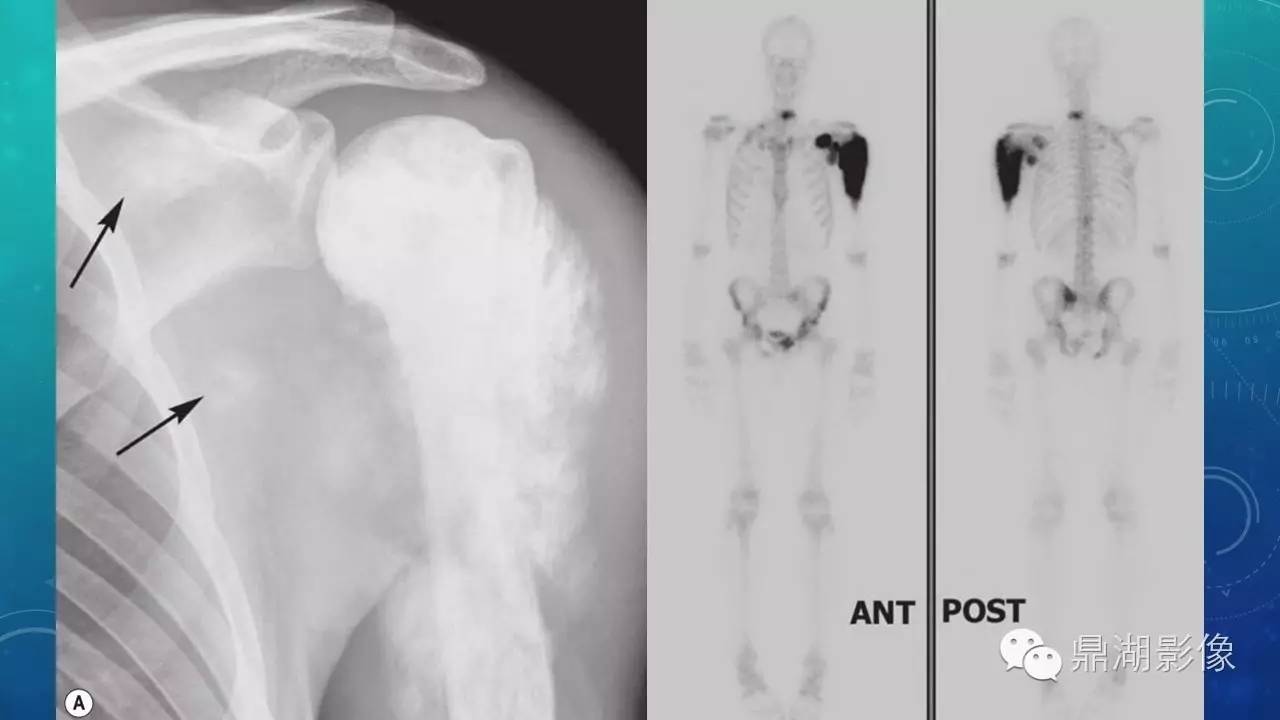

软组织钙化(的鉴别)